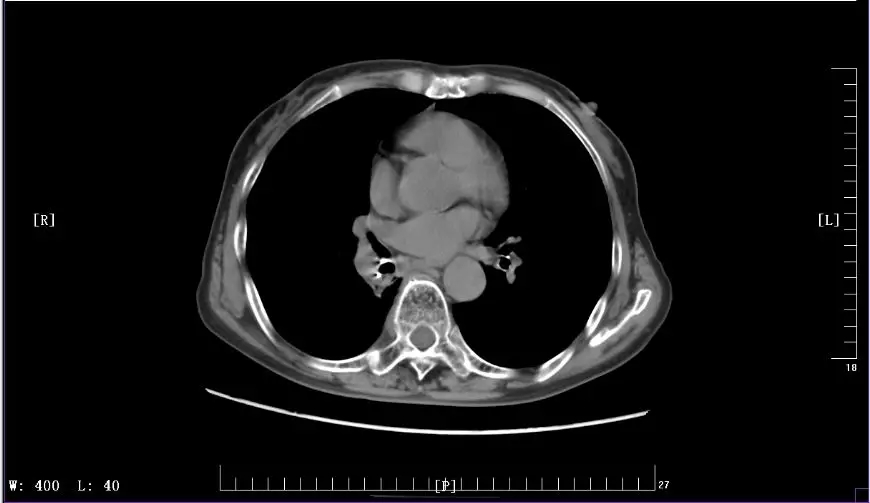

下圖是徐麗參加KEYNOTE-407臨床試驗(yàn)前后CT影像對(duì)比圖:

2017年11月治療前CT影像